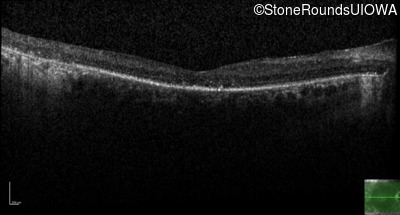

Age at visit: 59 years